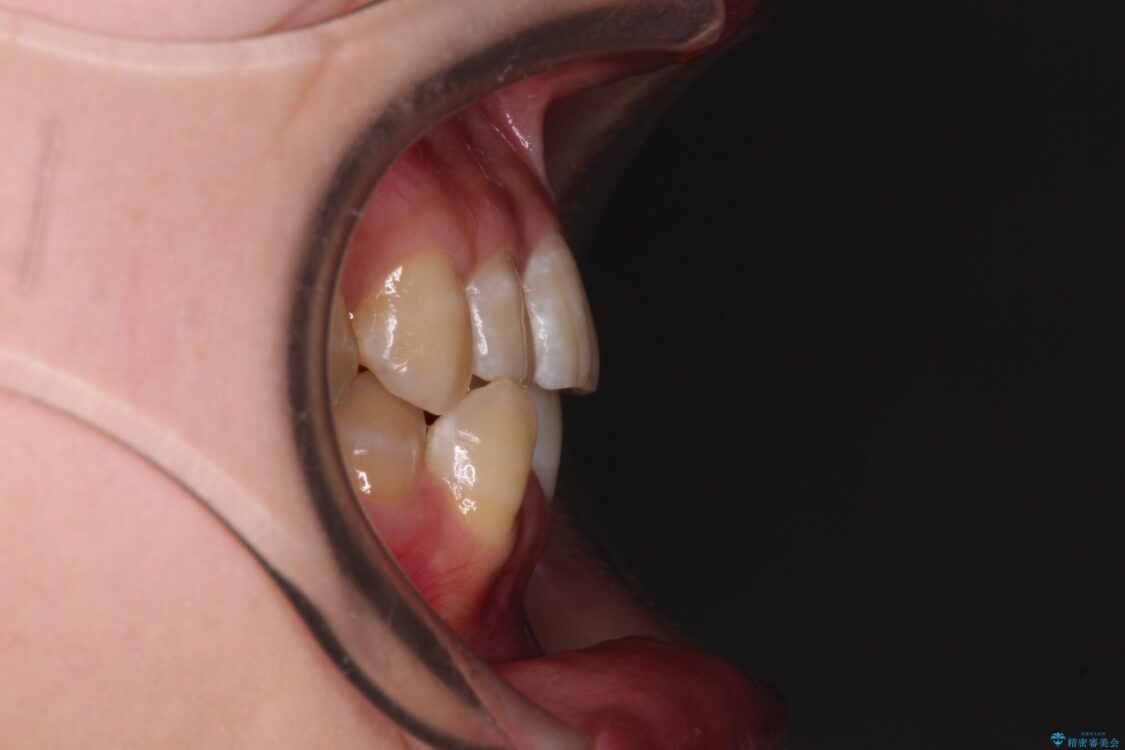

下顎の八重歯を気にして来院された患者様です。

下顎前歯にデコボコが集中していたため、顎間ゴムによる後方移動とIPR(歯と歯の間を削ること)により歯列を整えることとしました。

治療前、下顎前歯のデコボコが集中しており、奥歯の咬み合わせは、上顎に対して下顎が前方位にある状態でした。下顎の歯列を後方へ移動させる治療はインビザラインの得意とするところですので、1年程度で無事に治療を終えることができました。

治療前

• 【モニター】下顎前歯のデコボコをインビザラインできれいに 治療前画像